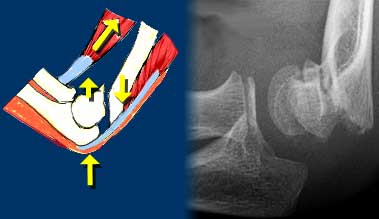

Injury to the elbow joint is usely the result of hyperextension or extreme valgus due to a fall on the outstretched arm.

Scroll through the images on the left to see how hyperextension leads to a supracondylar fracture.

The hemarthros will result in a displacement of the anterior fat pad upwards and the posterior fat backwards.

Distention of the joint will cause the anterior fat pad to become elevated and the posterior fat pad to become visible.

An elevated anterior lucency or a visible posterior lucency on a true lateral radiograph of an elbow flexed at 90? is described as a positive fat pad sign (figure).

Hemarthros results in an upward displacement of the anterior fat pad and a backward displacement the posterior fat.